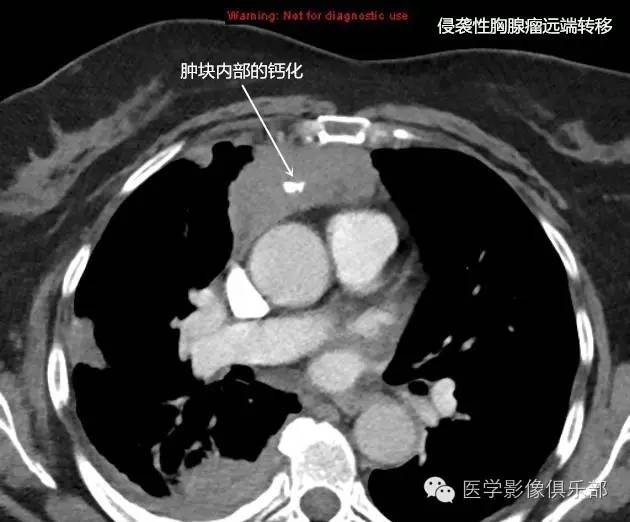

前纵隔巨大胸腺瘤切除 右侧中上肺切除术 胸膜多发结节切除术

影像基础胸腺瘤的分类分期及ct表现归纳

胸腺上皮性肿瘤最新组织学分型临床分期影像表现